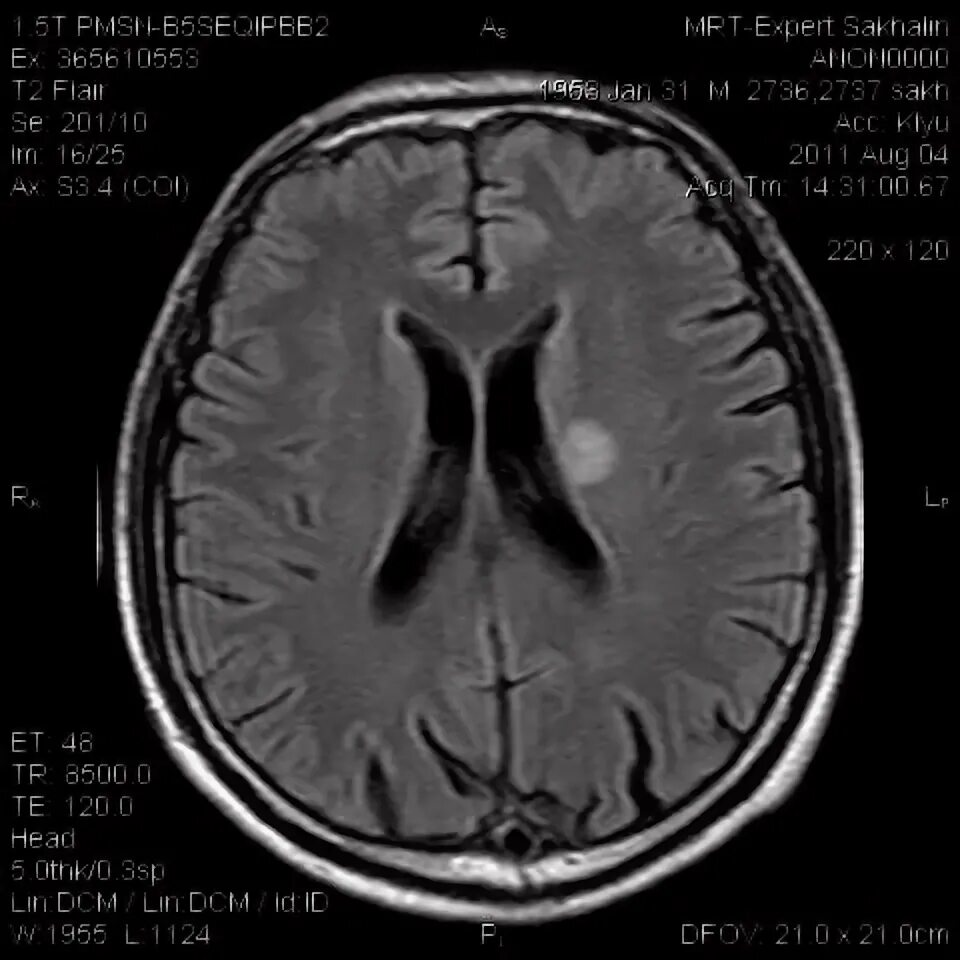

Мрт головного мозга мосто мозжечкового угла